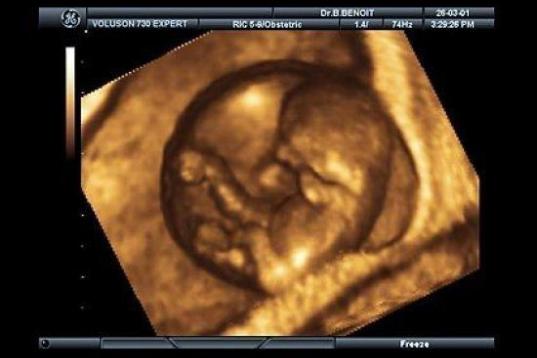

En esta galería puedes ver en fotos como es el desarrollo de un feto de semana en semana:

Desarrollo del feto, en fotos